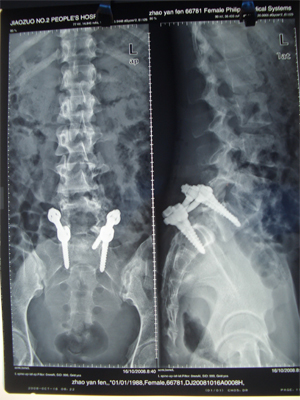

患者,28岁,腰疼,双下肢疼2年,加重3月,可串到小腿。诊断为腰椎滑脱,手术固定复位融合,术后症状马上消失,已上班2年。

手术前片子,神经受压严重

手术后复位